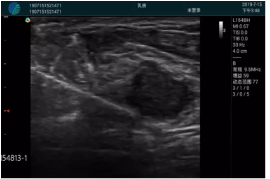

M20實(shí)時(shí)引導(dǎo):向包塊后方間隙注射利多卡因

清晰顯示腺體內(nèi)低回聲快影,邊界清晰,包膜較光滑

確定進(jìn)針路徑并實(shí)時(shí)監(jiān)測(cè)抽吸針與腫塊位置關(guān)系

抽吸針進(jìn)入腫塊內(nèi)部進(jìn)行旋切

抽吸過程中可見腫塊明顯縮小,并根據(jù)腫塊位置改變針道位置

抽吸旋切后再進(jìn)行超聲復(fù)查,原腫塊區(qū)域未見殘留組織及出血